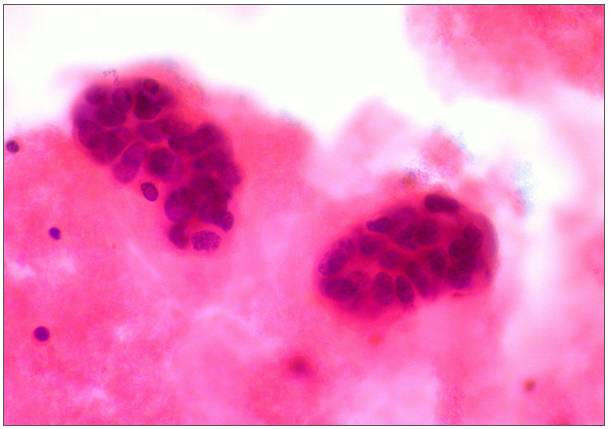

培养体系中的乳腺癌细胞能够在氨存在下的情况下快速增殖,而当癌细胞内的氨代谢途径受到抑制时,小鼠体内乳腺癌细胞的增殖速度就会得到大幅抑制。

研究人员发现,乳腺癌细胞不但不会受到氨累积的消极影响,反而还会比没有氨累积的正常细胞生长得更快。